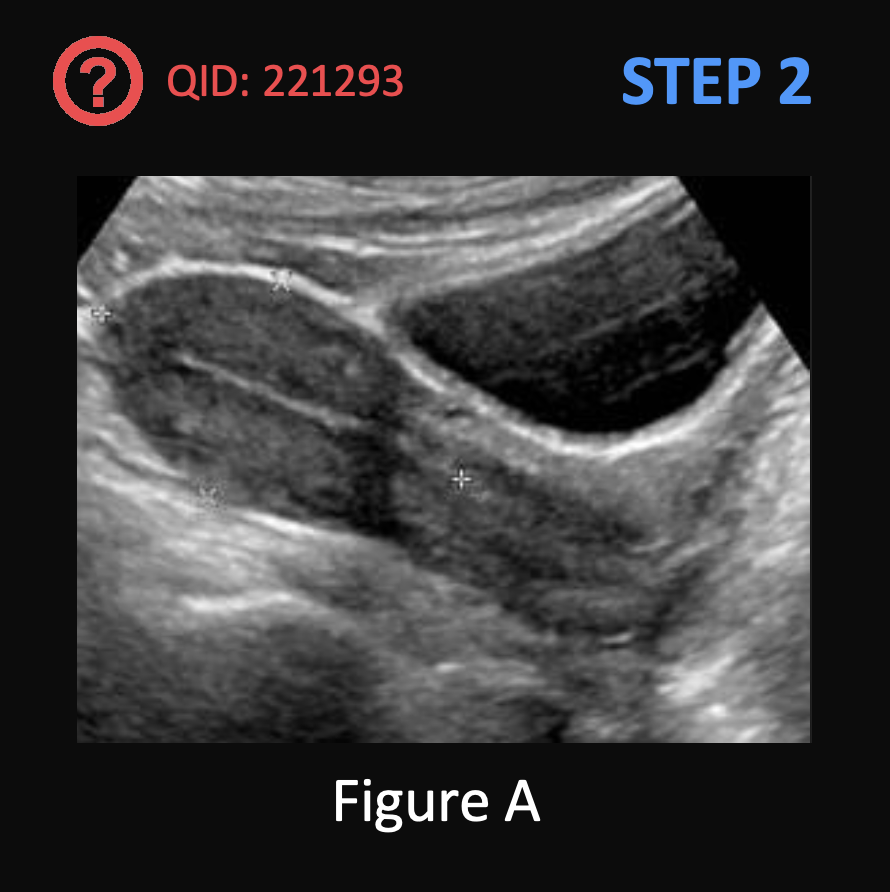

A 33-year-old woman presents to her primary care physician with a 2 month history of discoloration of the skin around her axillae. She first noticed the changes when she returned from a cruise but it has gotten worse over time. She originally thought that she was sunburned but there was no pain. Her medical history is notable for type 2 diabetes mellitus and polycystic ovarian syndrome. Her medications include metformin and a combined estrogen-progestin oral contraceptive. Her temperature is 98°F (36.7°C), blood pressure is 126/78 mmHg, pulse is 82/min, respirations are 12/min, oxygen saturation is 100% on room air, and BMI is 32 kg/m^2. Examination is notable for the finding shown in Figure A in both axillae and the neck. Which of the following other skin findings is associated with the underlying pathology responsible for this condition?